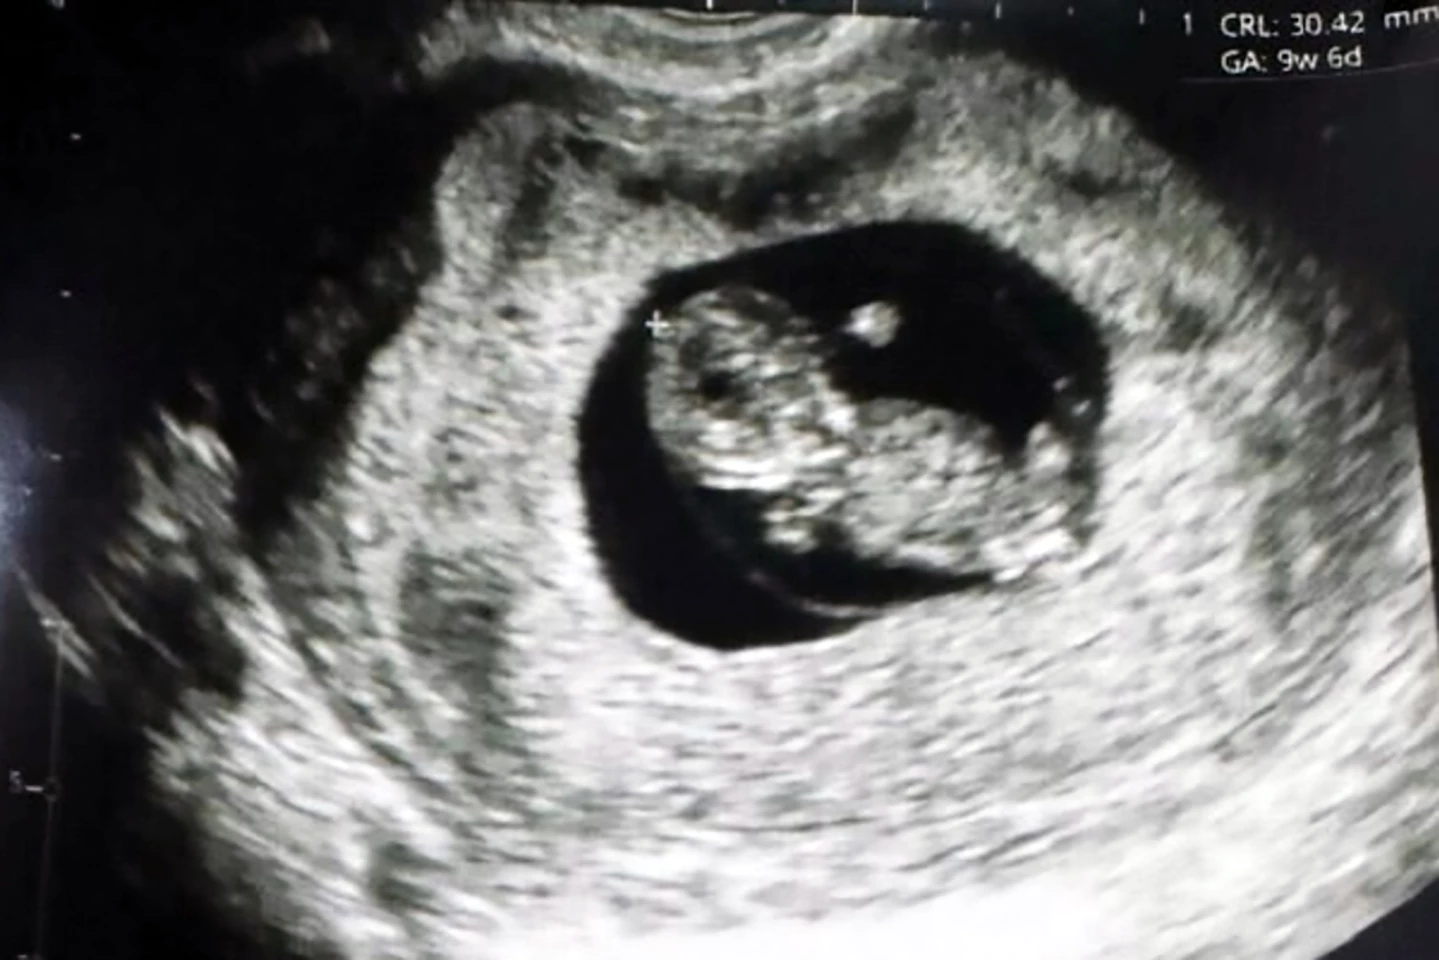

The mother of the world’s first 'Fertilo baby,' born in the Santa Isabel Clinic in Lima, Peru, couldn’t be happier.